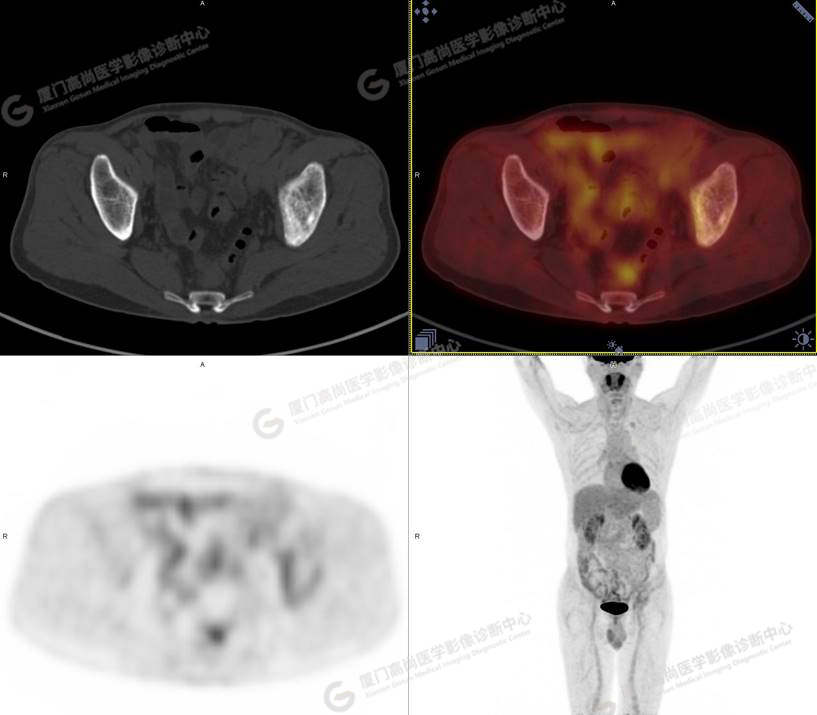

PET/CT影像圖

圖1

圖2

圖3

圖4

PET/CT所見:左側(cè)髂骨、髖臼及恥骨骨質(zhì)密度不均勻增高,CT值約594Hu,邊緣模糊,放射性攝取輕度增高,SUVmax 2.79,周圍軟組織未見明顯異常。